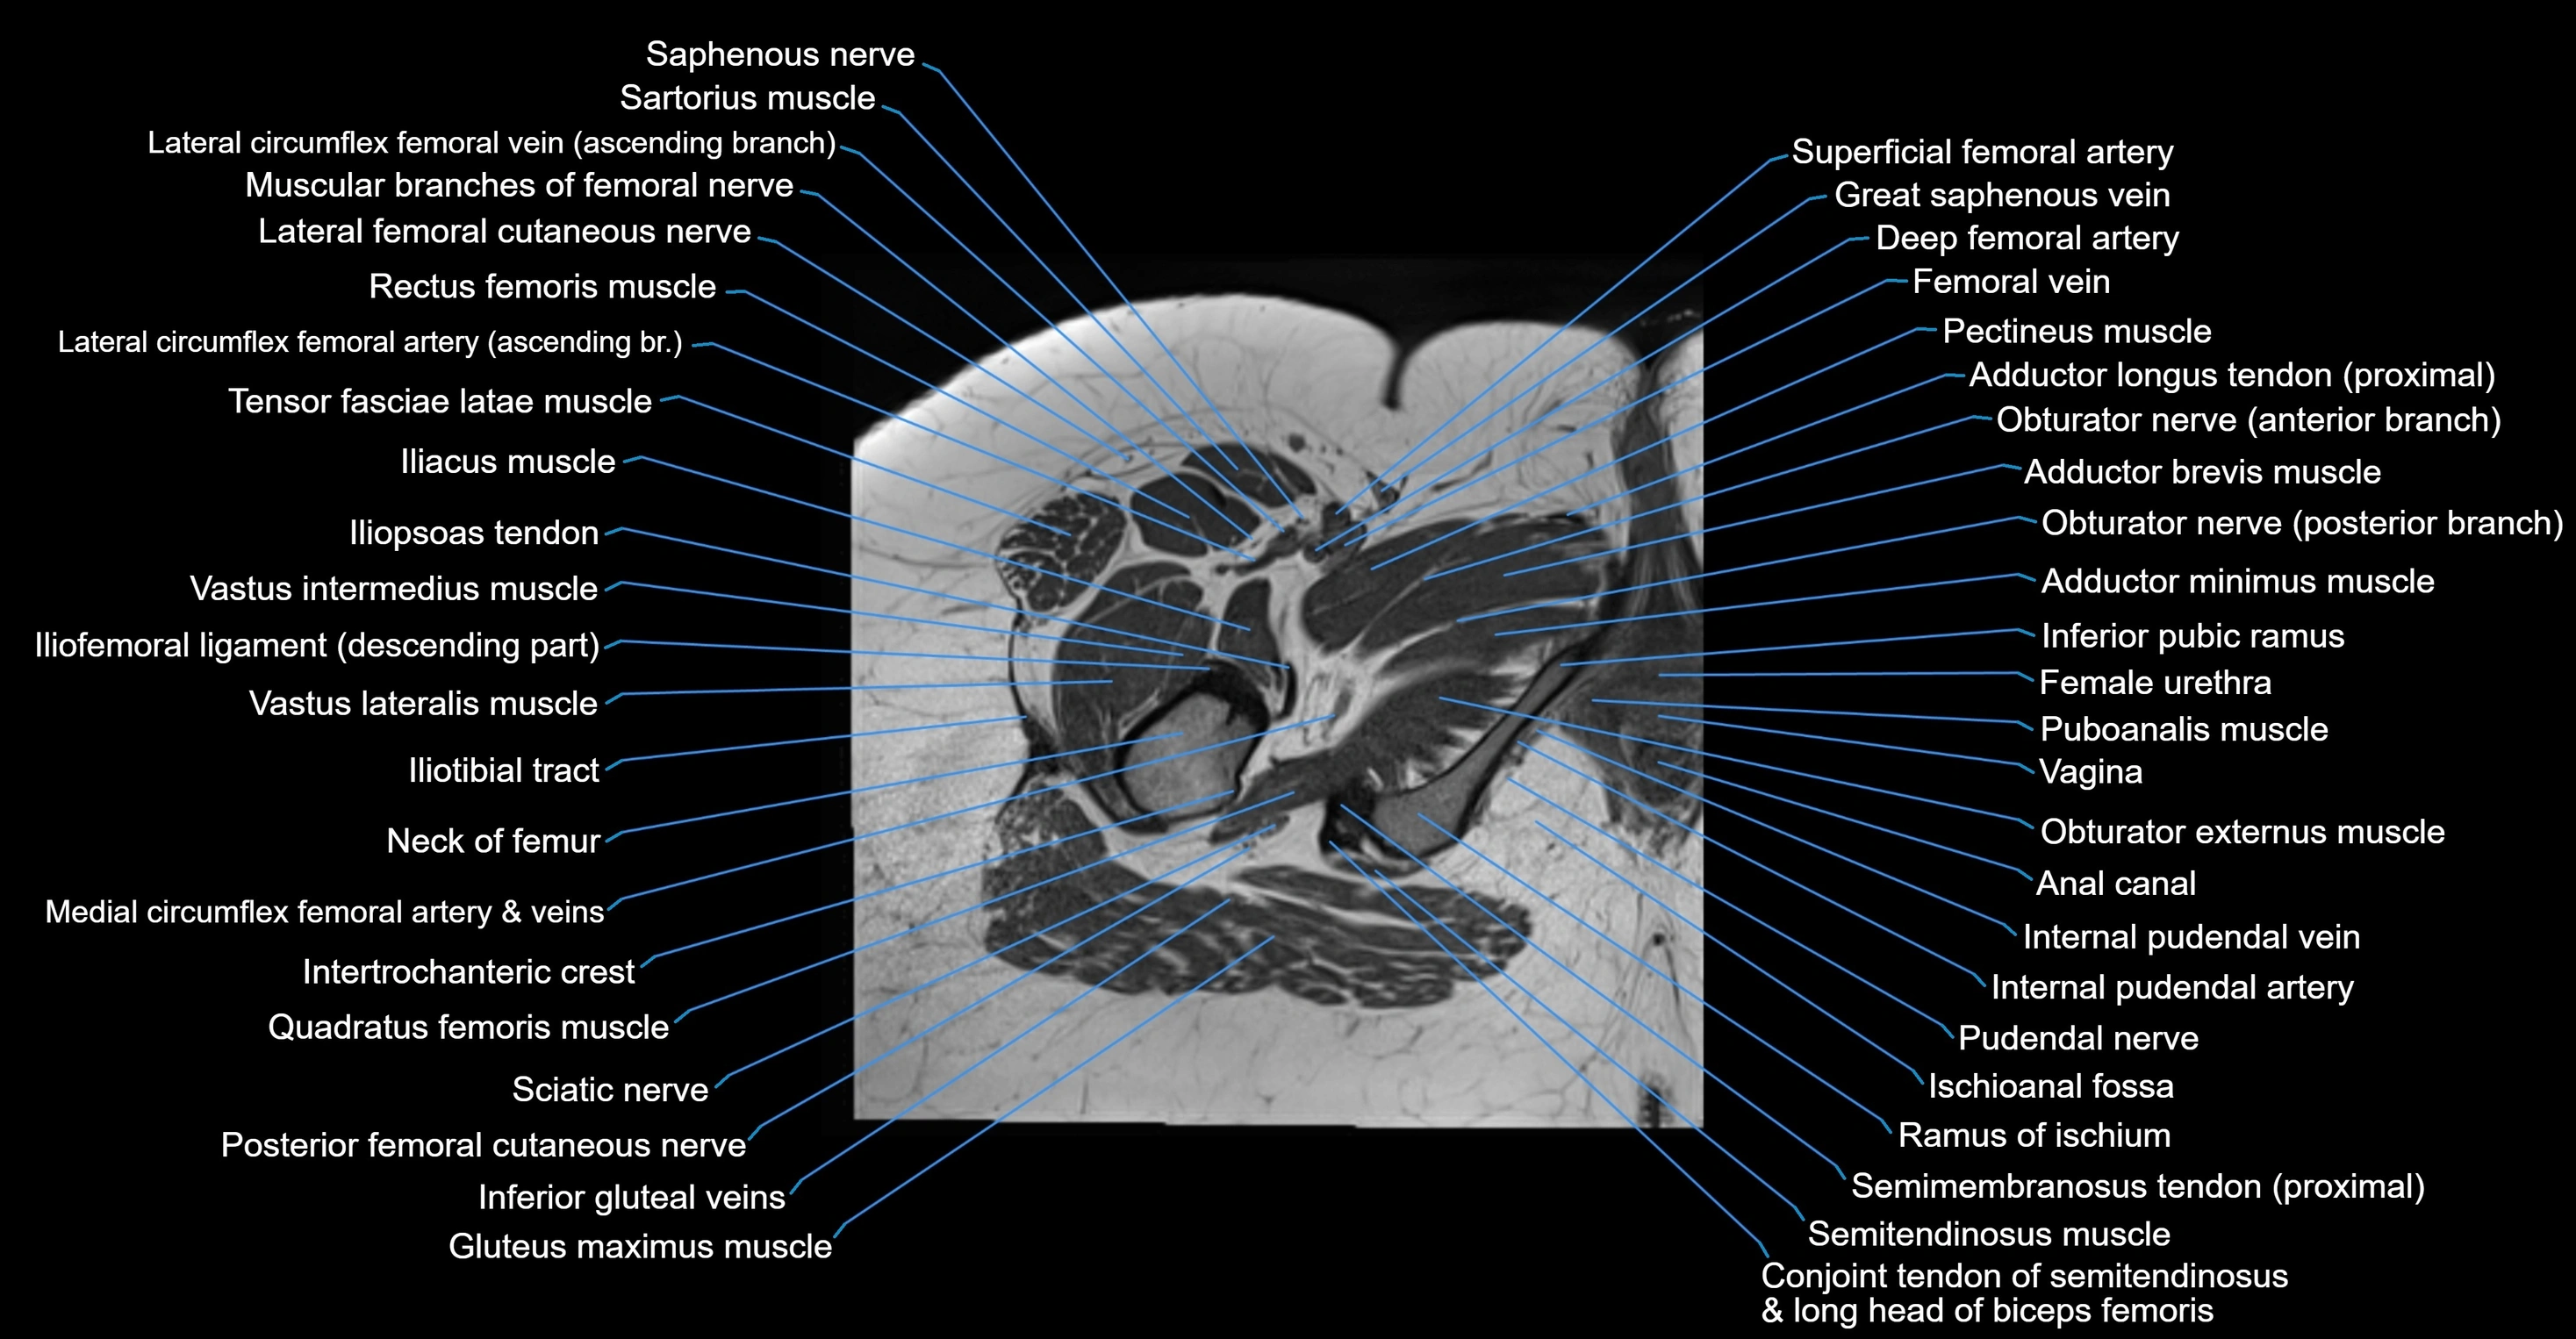

- Adductor brevis muscle

- Adductor longus muscle

- Adductor magnus muscle

- Adductor minimus muscle

- Gracilis muscle

- Iliopsoas tendon

- Iliotibial tract

- Inferior pubic ramus

- Ischioanal fossa

- Neck of femur

- Obturator externus muscle

- Pectineus muscle

- Posterior femoral cutaneous nerve

- Puboanalis muscle

- Pudendal nerve

- Quadratus femoris muscle

- Ramus of ischium

- Rectus femoris muscle

- Saphenous nerve

- Sartorius muscle

- Semimembranosus tendon (proximal)

- Superficial femoral artery

- Tensor fasciae latae muscle

- Vastus intermedius muscle

- Vastus lateralis muscle